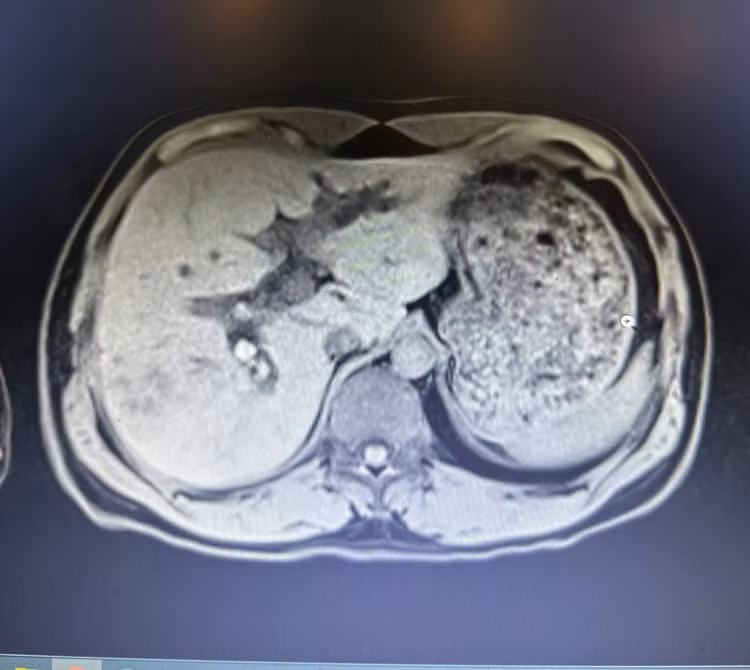

Người bệnh nhập viện trong tình trạng đau bụng kéo dài. Qua thăm khám lâm sàng và thực hiện các xét nghiệm cần thiết, đặc biệt là chụp cộng hưởng từ gan mật (MRI), các bác sĩ phát hiện hệ thống đường mật trong gan hai bên giãn. Đường mật gan phải có nhiều sỏi xếp chuỗi, viên lớn nhất kích thước khoảng 16 x 15 mm; ống mật chủ giãn 14 mm, chứa hai viên sỏi kích thước khoảng 15 mm.

Hình ảnh chụp cộng hưởng từ (MRI) cho thấy hình ảnh sỏi trong gan xếp chuỗi rất rõ (màu trắng) - Ảnh BVCC